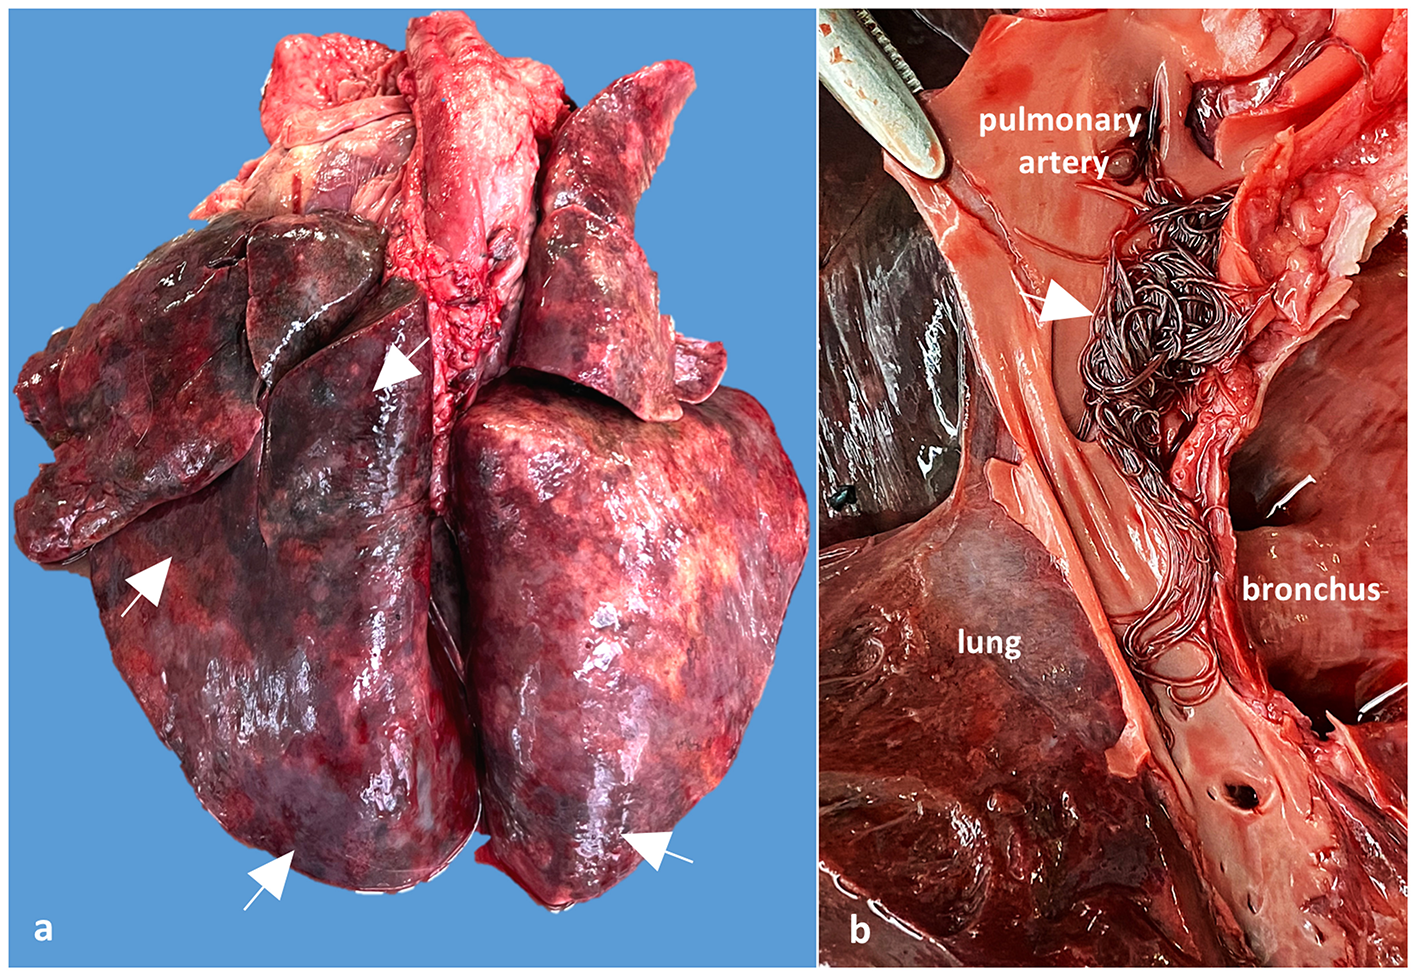

The main postmortem changes consisted of severe cyanosis and bilateral pulmonary densification with multiple areas of hemorrhage and necrosis (cobblestone appearance) (Figure 2a). The pulmonary arteries and right ventricle contained numerous adult nematodes of A. vasorum, measuring between 2 and 2.5 cm in length (Figure 2b). A single adult female of Dirofilaria immitis was found in the right ventricle of the heart. Cardiomegaly with hypertrophy of the right ventricular wall because of chronic pulmonary lesions and hypertension (cor pulmonale) was also observed. The tracheobronchial lymph nodes were edematous and hemorrhagic. The gastric mucosa from the body region showed granular to round white-gray nodules, varying between 2 and 5 mm, interpreted as nodular gastritis. No other significant gross changes were noticed.

Figure 2

Case 2, Gross examination of the lungs and pulmonary arteries: (a) Lungs shows numerous dark red areas of densification, suggesting verminous pneumonia with necrosis and hemorrhages (arrows); (b) Detail of the opened pulmonary artery showing numerous adults of A. vasorum in the pulmonary artery (arrow).